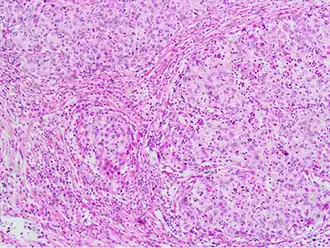

Invasive cervical squamous cell carcinoma on H&E histopathology and Ki-67 immunohistochemistry. The latter correlates well with the degree and level of dysplasia.[77] -